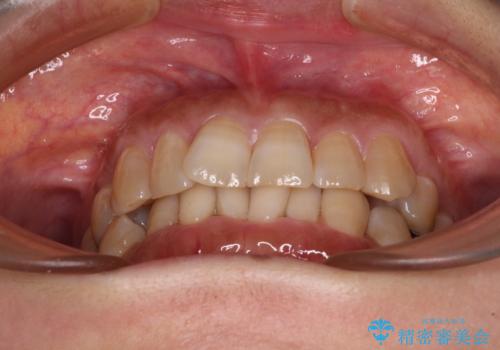

ディープバイトと前歯のデコボコ インビザラインによる矯正治療

インビザライン特有の奥歯の噛みにくさが治療後半に発言しましたが、無事に終了させることができました。